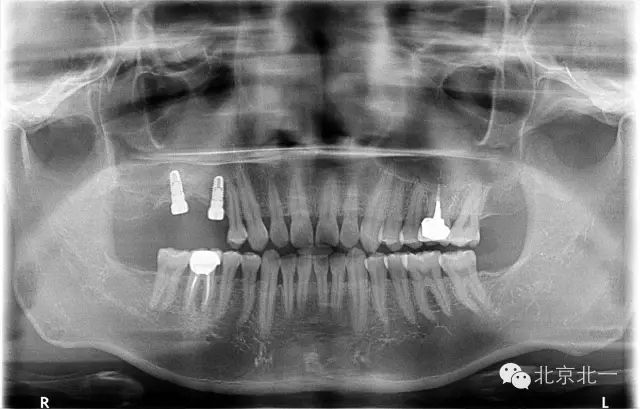

圖二:手術(shù)前全景片

圖十七:縫合。非潛入

圖二十三:種植后當(dāng)天全景片。